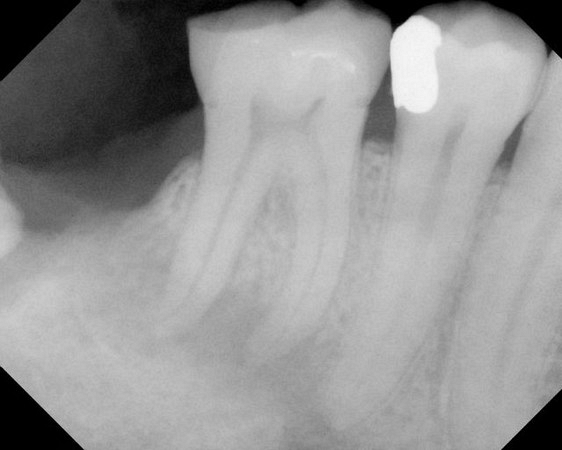

See xrays of before and after a root canal is completed below